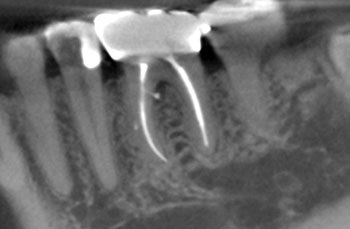

Case 2: A U-shaped lesion

Tooth #30 presented with a diagnosis of previously treated and symptomatic apical periodontitis. The radiographic lesion encompassed both sides of the mesial root, forming a U-shaped lesion. Periodontal probing extended to the apex. The prior endodontic root preparations were relatively large, compared with the root canals on the patient’s other untreated teeth. Because the bone loss associated with a U-shaped lesion encompasses both sides of a root, it might be considered even more indicative of a potential VRF than a J-shaped lesion.

This patient had been examined by an endodontist, who recommended extraction because of a VRF. Although multiple risk factors were identified, no fracture was seen upon access, and this tooth was successfully retained through nonsurgical retreatment.

Fig. 5: Preop PA.

Fig. 6: Preop CBCT.

Fig. 7: Recall PA.

Fig. 8: Recall CBCT.